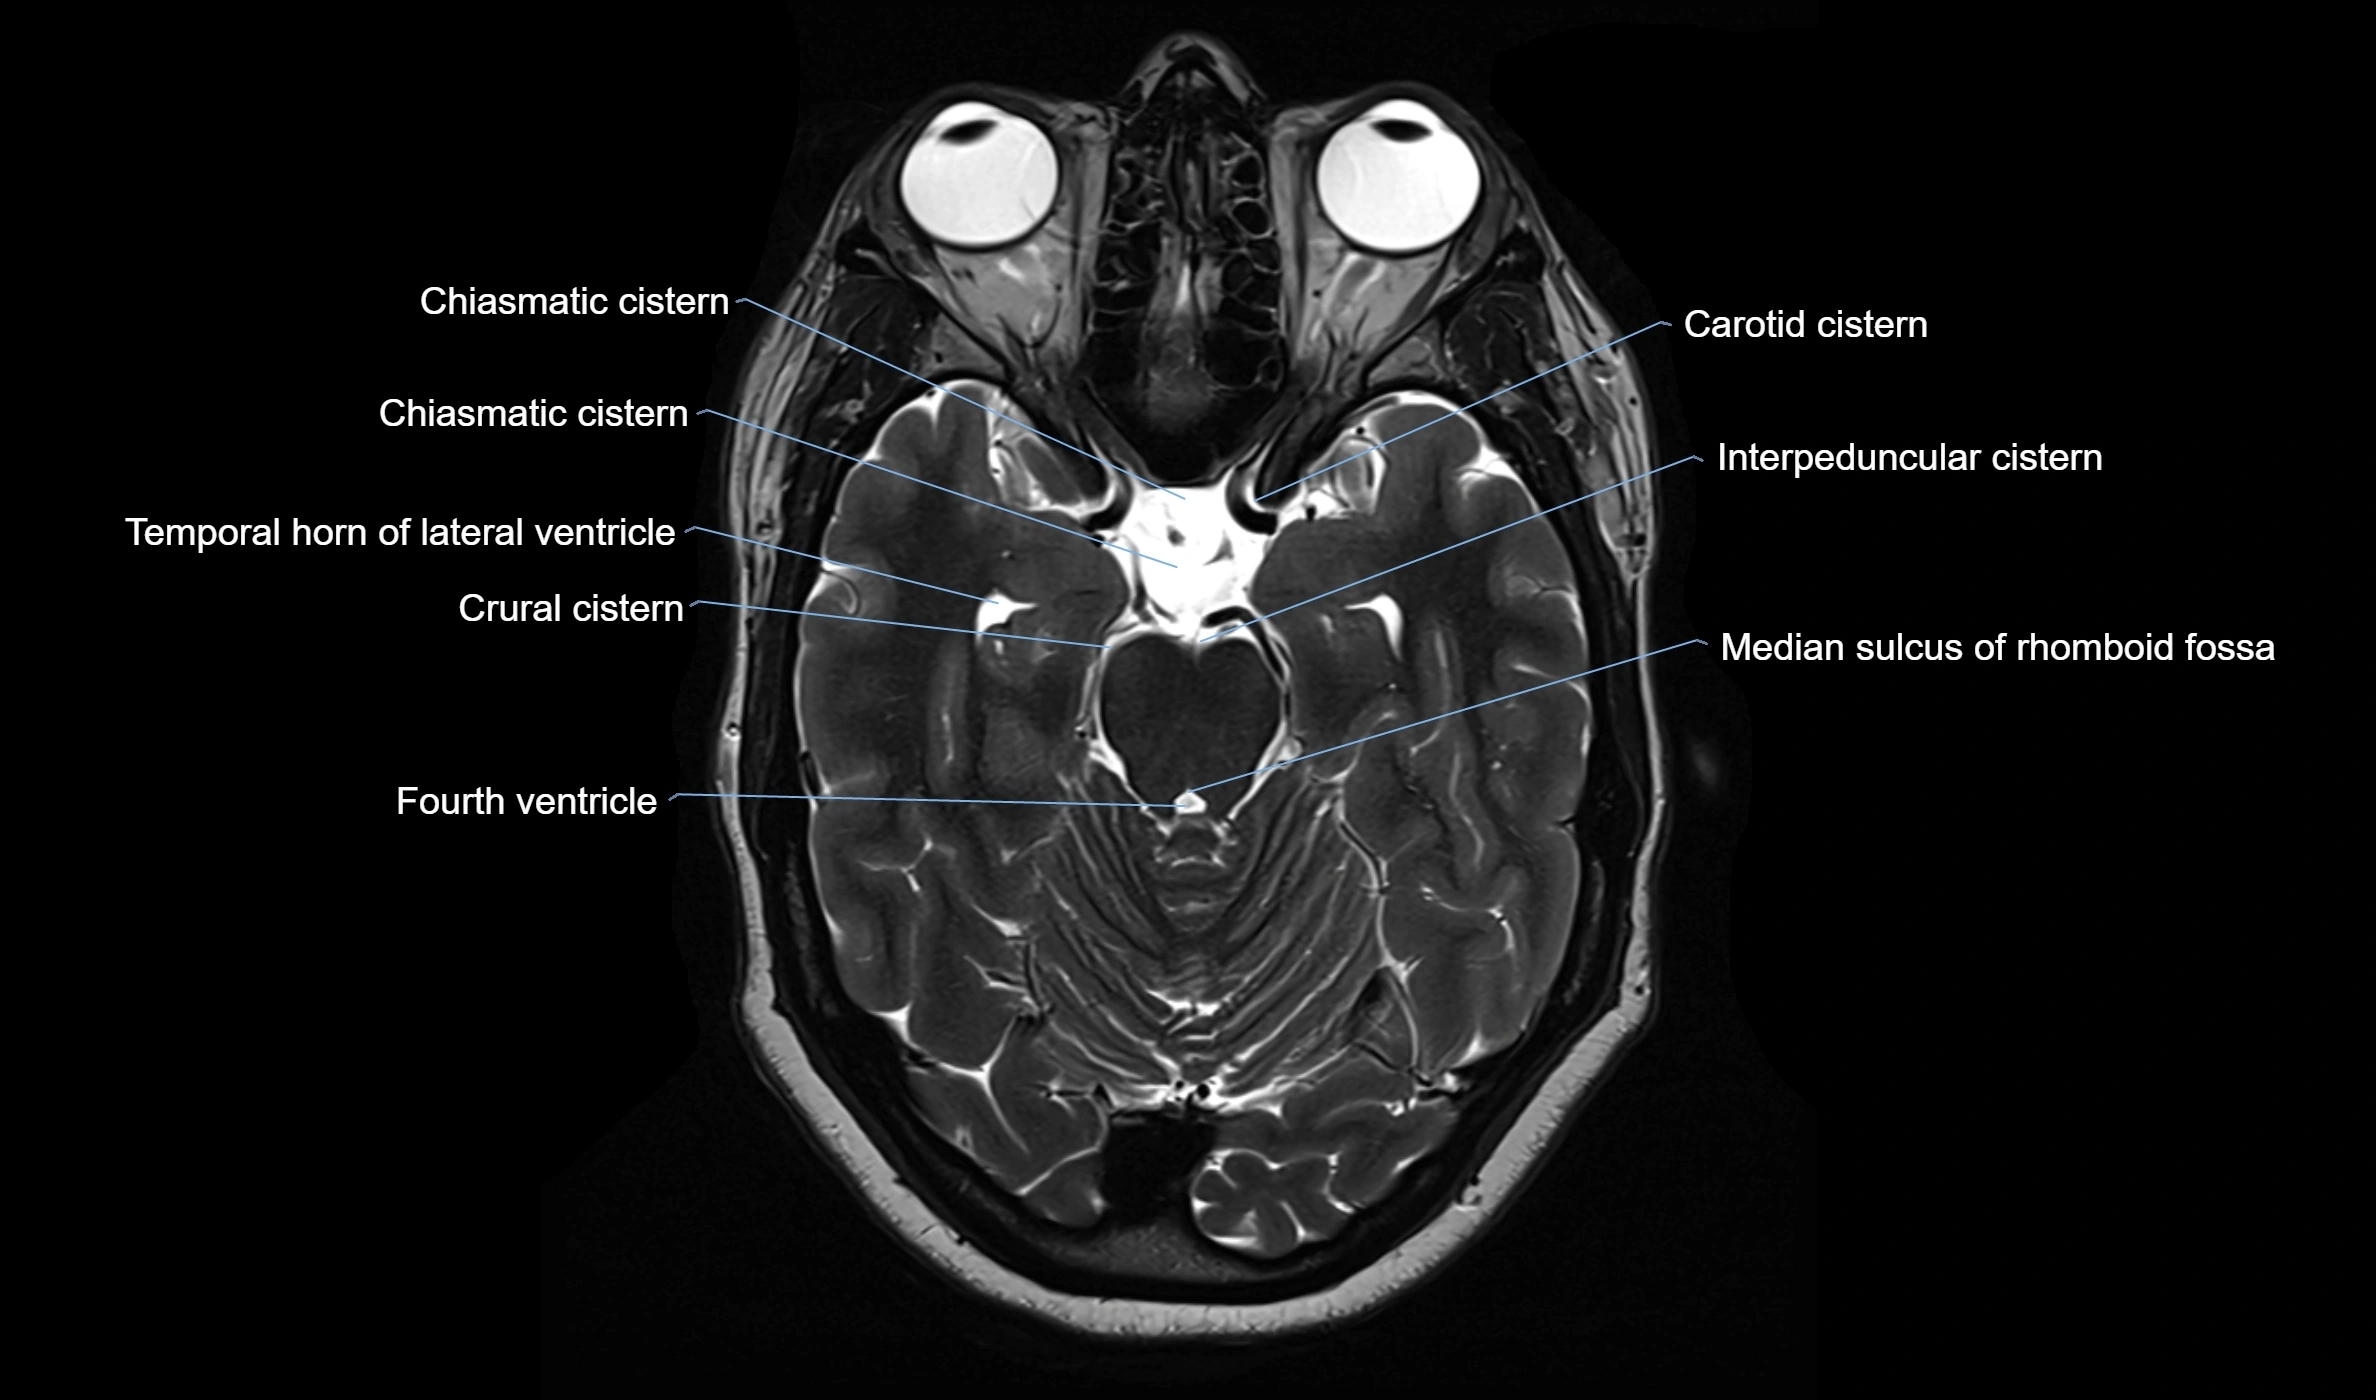

MRI images

image